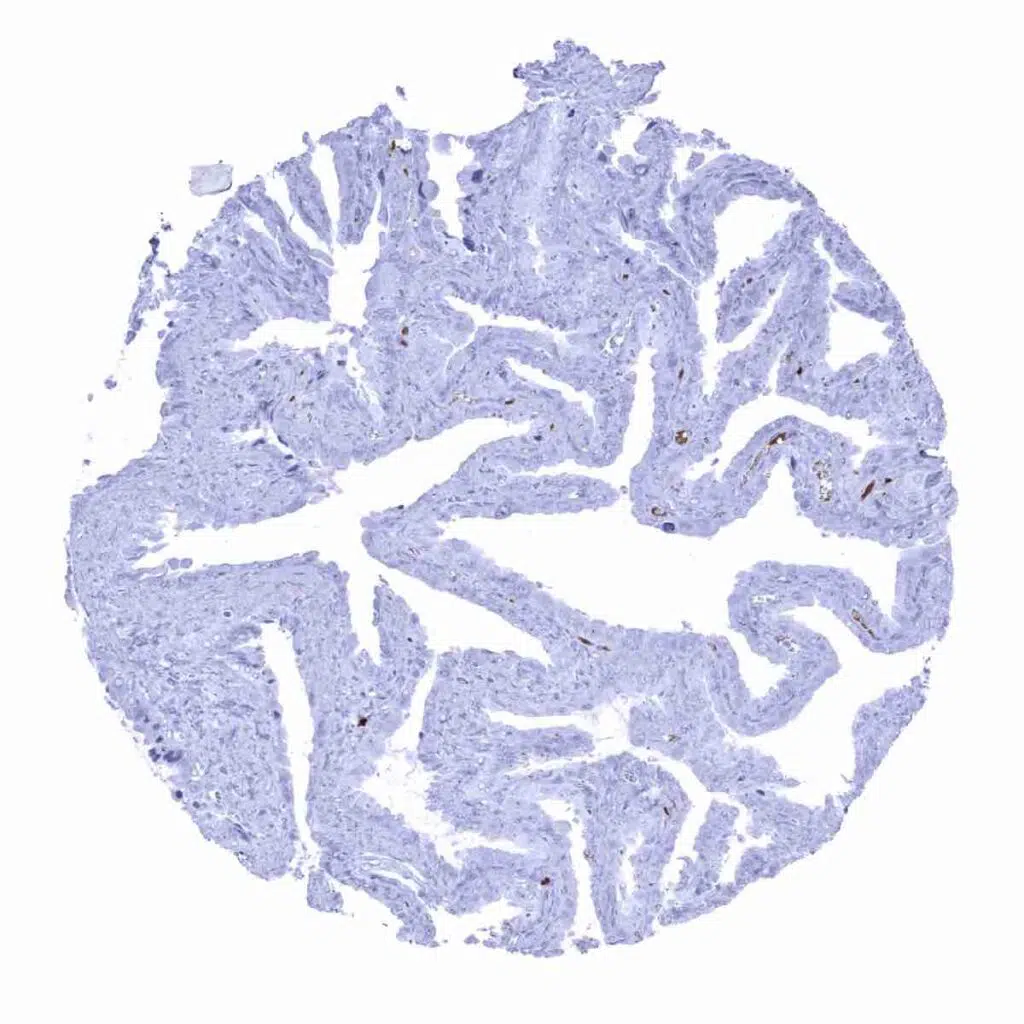

Uterus, endocervix